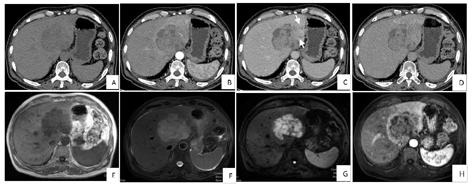

影像学检查:(1)CT平扫及增强(图1):肝左叶见类圆形略低密度影,最大截面约8.8 cm×7.1 cm,增强扫描不均匀延迟强化,并可见肝动脉、门静脉分支走形入病灶内,静脉期病灶边缘见两处低强化影向左外叶延伸(2处),邻近肝实质见斑片状强化影,右侧心膈角区及肠系膜区多发淋巴结影,大者大小约1.1 cm×0.8 cm,增强扫描轻度强化。(2)MRI平扫及增强(图1):肝左叶见团块状长T1、长T2信号影,DWI扫描示病灶主体呈高信号,边缘见条形高信号影向左外叶延伸(2处),同反相位无信号衰减,增强扫描病灶周边较明显强化,静脉期及延迟期强化程度减低,内部可见线样延迟强化影,另肝左叶动脉期见片状强化。(3)常规腹部超声及超声造影(图2):肝内低回声实性占位,边界清,形态欠规则,内及血流信号,超声造影动脉早期快速偏高增强,可见动脉自然穿过,无狭窄、扭曲,28 s开始廓清,延迟期持续低增强,呈"快进快出"恶性肿瘤模式。(4)PET-CT(图3):肝左外叶为主可见大小约8.8 cm×7.1 cm的低密度肿块显示,其内密度不均,代谢增高,伴左侧肱骨上段、胸6椎体附件、左侧第6肋可见多发溶骨性及成骨性骨质破坏灶,代谢增高,右侧心膈角区、腹主动脉旁淋巴结显示,大者约1.5 cm×0.5 cm,代谢增高。

本病的主要影像学表现为肝内单发病变、多发结节或弥漫型浸润,常伴有多部位、多组淋巴结同时受侵及其他结外脏器受侵。PHL以孤立性肿块多见,而SHL以多发结节或弥漫浸润多见[2]。根据本例影像表现,肝内虽为孤立性肿块,但结合患者淋巴结肿大明显,考虑为SHL。结合文献,笔者认为,本病的影像表现有以下特征:(1)表现为门静脉周围肿块样及分支样浸润病灶,可能与肝脏淋巴组织主要分布于这一区域有关,仅有很少病例报道这一征象[3]。此征象也可在朗格汉斯细胞组织增生症、肝细胞癌、胆管细胞癌的淋巴管扩散出现,但门静脉周围淋巴瘤无血管侵犯或占位效应。(2)增强扫描呈渐进性轻至中度持续强化,提示肿瘤乏血供,可能与肿瘤细胞密集度高而间质、微血管成分稀疏有关,与文献报道相符[4]。本病例肿瘤内未强化区经病理证实为肿瘤的坏死区域,与既往文献报道一致[5,6],亦有学者认为是纤维组织所致的类似肝脏局灶性结节样增生(focal nodular hyperplasia,FNH)的瘢痕结构[7],则表现为延迟强化,病理基础为肝星状细胞所致的肝纤维化对慢性肝损伤产生的修复反应。另外本病例病灶动脉期周边环形强化,静脉期及延迟期强化程度减低,Maher[8]认为此现象与病灶侵犯邻近正常肝组织导致的脉管炎有关。(3)增强扫描见"血管漂浮征",即病灶周围血管表现为受压变窄、推移、变形,但多无破坏中断,可见连续血管影,其病理学基础可能与肿瘤起源于肝脏间质,沿着肝组织的解剖结构浸润性生长,而对肝内固有血管破坏轻微有关,因此被认为是肝淋巴瘤的特征性表现[2],对诊断具有重要意义。(4)MRI成像呈T1WI低信号,T2WI等或稍高信号,DWI示弥散受限,相对其他肿瘤更明显,这与淋巴瘤肿瘤细胞密集度高有关[4],动态增强表现同CT。